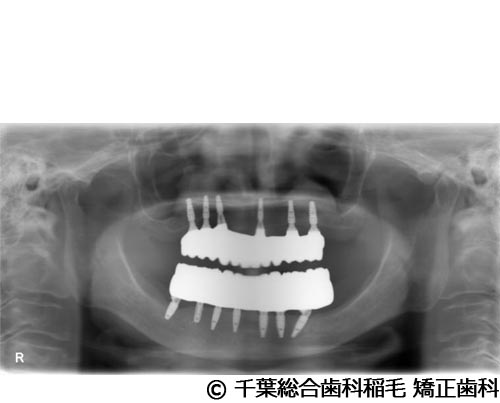

【症例5】All-on-6(オールオン6)

- 治療前

- 治療後

- 治療名

- All-on-6(オールオン6)

- 費用

- 7,500,000円(税込)

- 期間

- 10ヵ月

治療内容

-

患者様の症状

入れ歯が合わなくなり、お食事も満足にできないとご来院されました。

治療法

ご相談の結果、上顎はインプラントを6本、下顎は7本埋入し、All-on-6(オールオン6)という固定式のインプラント治療を行いました。

治療結果

入れ歯が動いてしまう煩わしさがなくなり、よく噛めるようになったと仰っています。

※治療結果は患者様によって個人差があります。